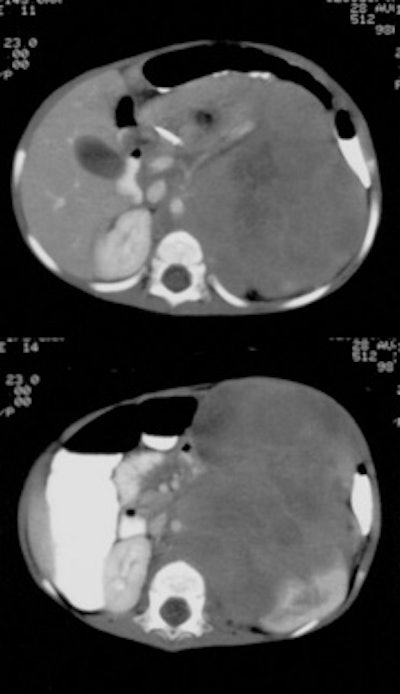

Neuroblastoma: Bone scan (left) demonstrated clearly abnormal tracer accumulation within the right 5th rib. There is ill-defined tracer accumulation within the left upper abdomen. In retrospect, there is asymmetric tracer activity in the right iliac wing, the left femoral neck and the distal left femoral metaphysis. These lesions are more clearly demonstrated on the MIBG exam (center). A right distal femoral metaphyseal lesion is also identified. Markedly abnormal MIBG accumulation can be seen in the patients large neuroblastoma (CT scan right). |